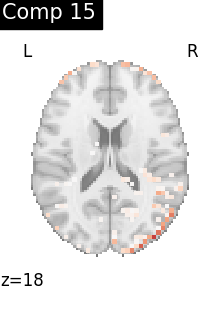

One plot of each component

for i, cur_img in enumerate(iter_img(dictlearning_components_img)):

plot_stat_map(

cur_img,

display_mode="z",

title=f"Comp {int(i)}",

cut_coords=1,

vmax=0.1,

vmin=-0.1,

colorbar=False,

)